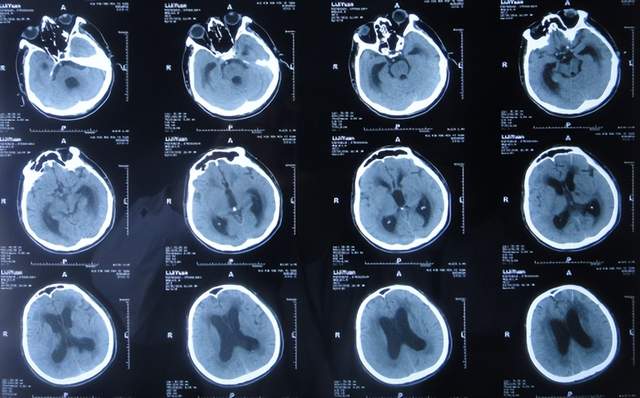

出院1个半月后,因患者病情无改善,家属想做脑室腹腔分流术,于2021年12月22日前往上级的山东省滨州市某三甲医院就诊,查头颅CT示脑积水(图-10);但腰椎穿刺检查示颅内压低;胸部CT有肺部脓肿(片子丢失),暂时给予抗感染治疗。

图-10:2021年12月22日头颅CT

给予抗感染治疗个月后即2022年1月17日,肺部脓肿明显变小(片子丢失),查头颅CT仍脑积水(图-11),未给予脑室腹腔分流术,建议暂时回家休养,但患者意识仍不好,不能走路,不能说话,体型变消瘦。

图-11:2022年1月17日头颅CT

2022年2月16日(脑出血后5个月零14天,继发脑积水4月余),为治疗脑积水,家属通过网上查询,并经确认后来到北京北亚骨科医院的李小勇脑脊液科。

二、在李小勇脑脊液科治疗过程和结果

2022年2月16日,入院时:意识模糊,精神差,喂流食,大小便失禁,体重减轻,体型消瘦(图-12)。既往病史:乙型肝炎病史,患有高血压十余年口服药物治疗,血压控制不佳;脑出血后血压偏低,脑出血后曾输注入人血白蛋白;患有Ⅱ型糖尿病二十余年,降糖药亦未规律服用,血糖控制不佳。

图-12:2022年2月16日入院时

入院时查头颅CT示脑积水(图-13);肺部CT示肺部感染(图-14)。

图-13:2022年2月16日头颅CT

入院次日,给予脑室外引流术,查头颅CT示脑室外引流术后状态(图-15)。

图-15:2022年2月17日头颅CT